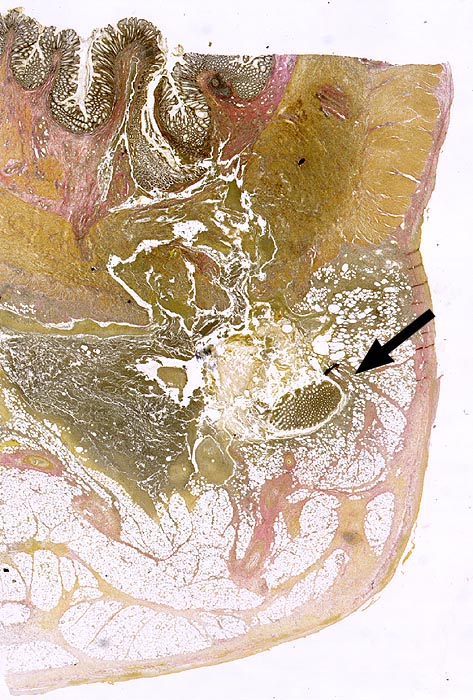

AP/ Divertikulitis

Divertikulitis

Darm, Anus

Kolon Sigma

Makroskopie

Virtuelles Präparat

Befund

Pathologischer Befund